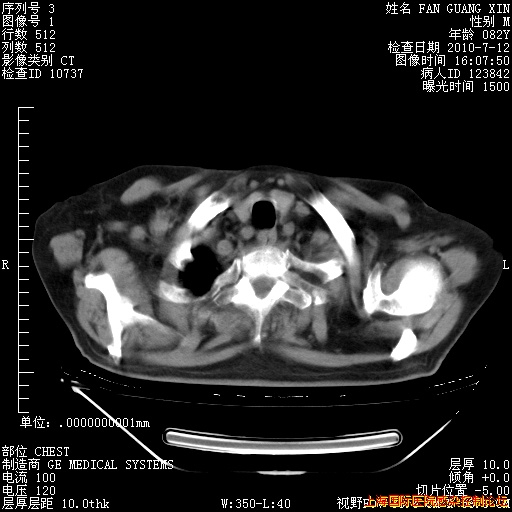

今天复查CT

今天CT

整整相隔30天的肺部CT好像有所好转啊。甲强龙减量第3天,需要观察体温。

海管,自昨日你和我通完话后,不知您岳父消化道症状有无缓解?体温怎样?阅读7.12日胸部ct,个人认为目前激素治疗是有效的,甲强龙减量是适宜的。因在抗痨治疗,需密切观察肝功、肾功能和血常规。不过,老年、长期住院和大量使用激素,很担心菌群失调发生